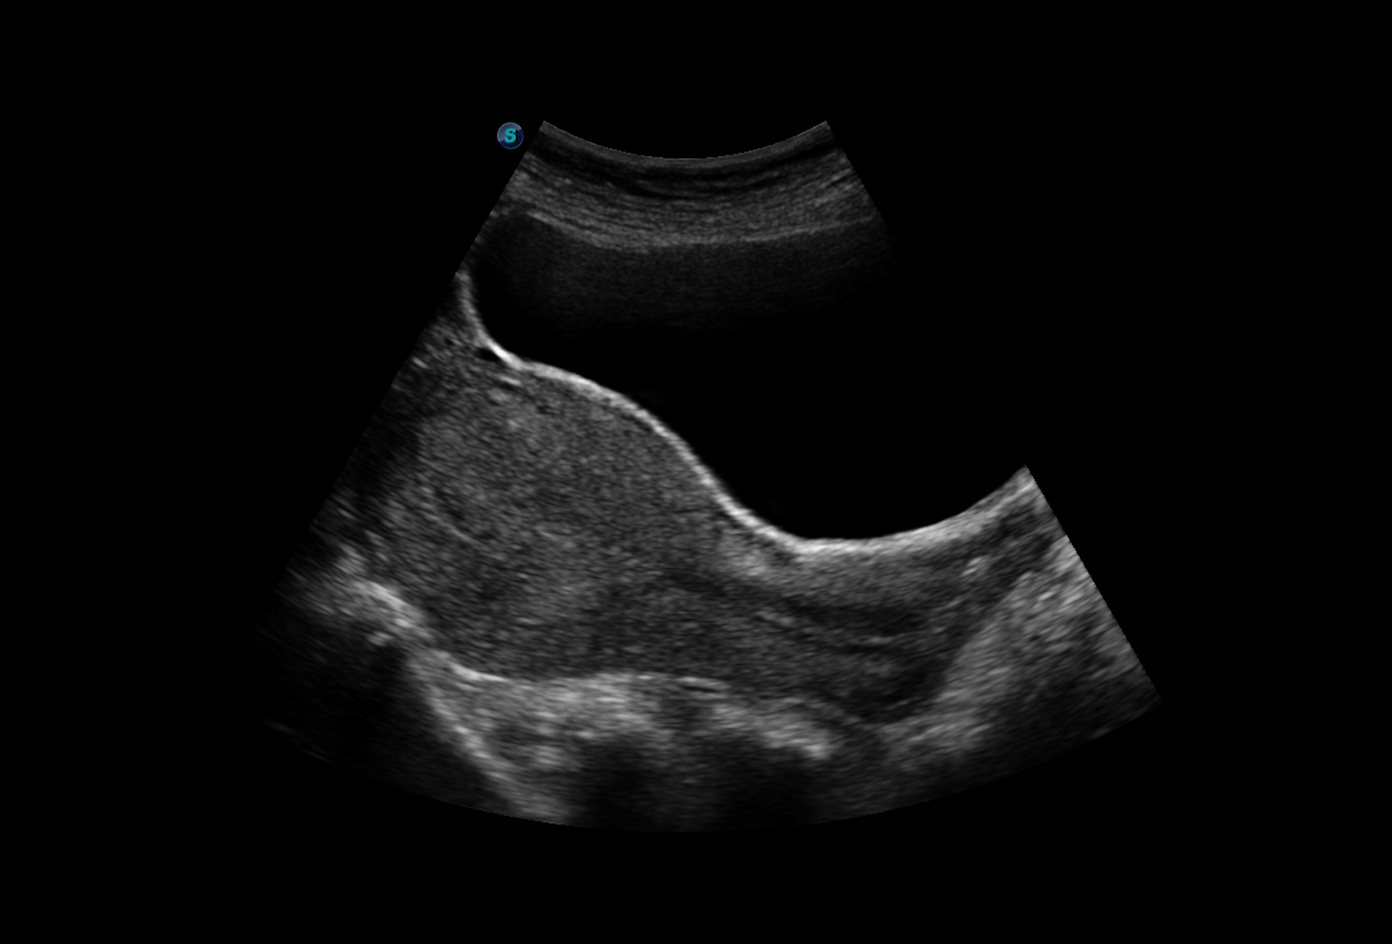

Chất lượng hình ảnh 2D trên máy siêu âm chuyên tim SonoScape P9:

Hình ảnh siêu âm Doppler thận sắc nét